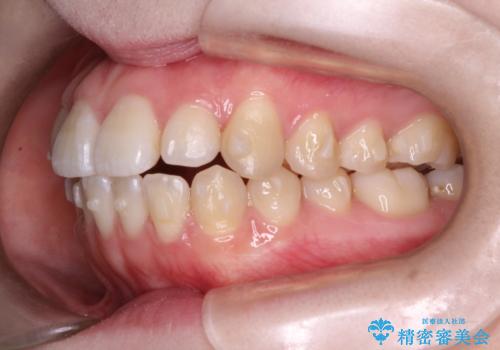

前歯にがたつきがあり、上下の歯が咬み合っていない状態でした。

歯列の横幅をひろげるのと、歯と歯の間をわずかに削ることにより、前歯のがたつきと、開咬を改善しました。